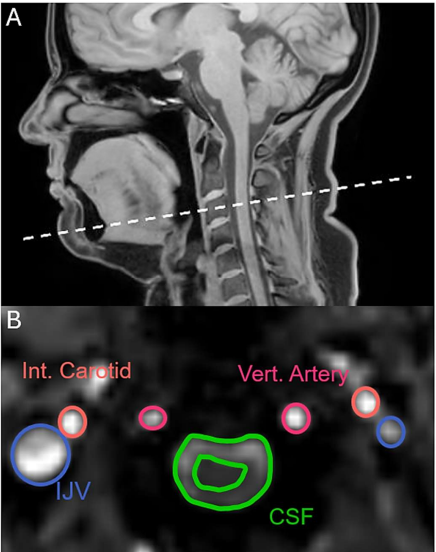

实验的核心监测点位于上颈椎水平(C3 椎骨平面)。研究人员可以实时量化脑脊液、颈内静脉血以及颈动脉血的流速与流向。

图 | 研究观察了血液和脑脊液流入和流出大脑的情况(来源:上述论文)

鉴于打哈欠和深呼吸的物理形态相似,研究人员原本预期它们的流体动力学模式也应该大同小异。然而,MRI 图像揭示了二者本质的区别。

正常呼吸时,脑脊液和血液表现为低频、低幅度的震荡,紧随心跳和呼吸节奏波动,整体净流量变化极小。

当你深吸气时,胸腔压力降低吸引静脉血下行流出大脑。为了维持颅内压力平衡,脑脊液通常会向上流入大脑填补空间。此时,血液向下,脑脊液向上,二者是反向运动的。

而在打哈欠的吸气阶段,这种平衡被打破了,脑脊液不再向上流动,而是反过来与静脉血步调一致,同步高速流离大脑,向脊柱方向排去。